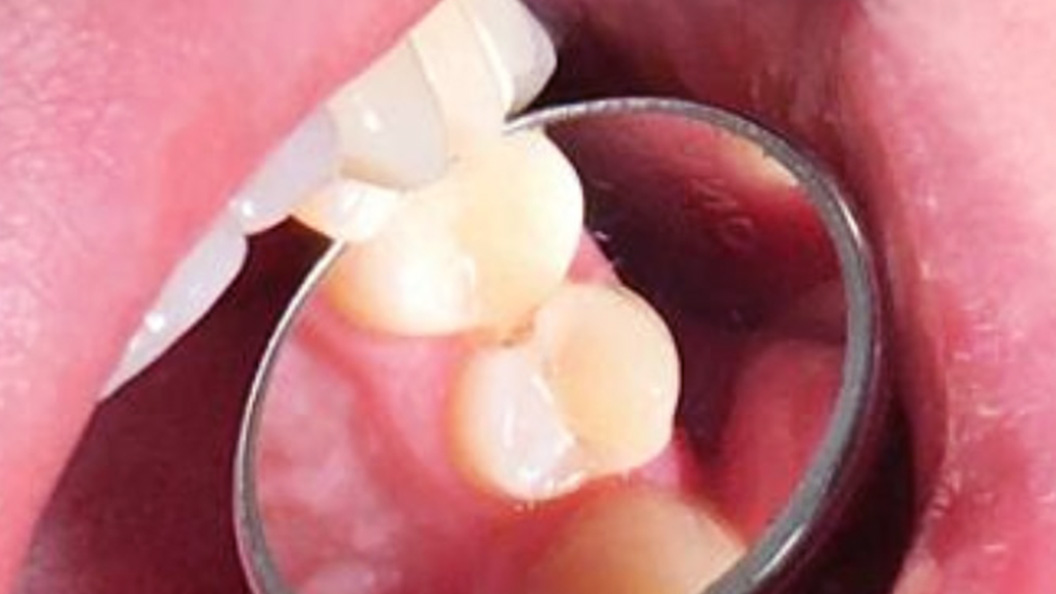

До и после лечения

В клинику «Стоматология Комфорта» обратился пациент с жалобой на острую и быстро проходящую боль в премоляре верхней челюсти в результате высокой чувствительности к холодному, а также застревание пищи. Врач Похилько Надежда Геннадьевна осмотрела полости рта и диагностировала глубокий кариес зуба 24, предложила пациенту пройти лечение с установкой световой пломбы Эстелайт.